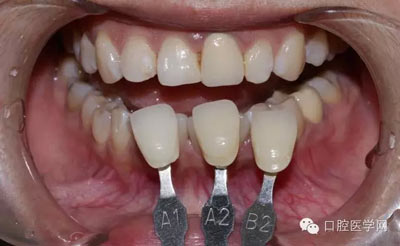

1、術(shù)前比色照

將比色照飽和度調(diào)到最低有助于牙齒明度的選擇

將比色照的飽和度調(diào)到最高有助于牙齒道飽和度選擇